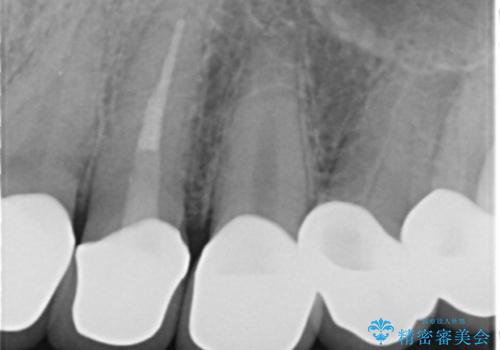

虫歯をしっかりと治療したのち、オールセラミッククラウンによる補綴治療を行いました。

クラウンの種類:オールセラミッククラウン スタンダード

シェード:NW0